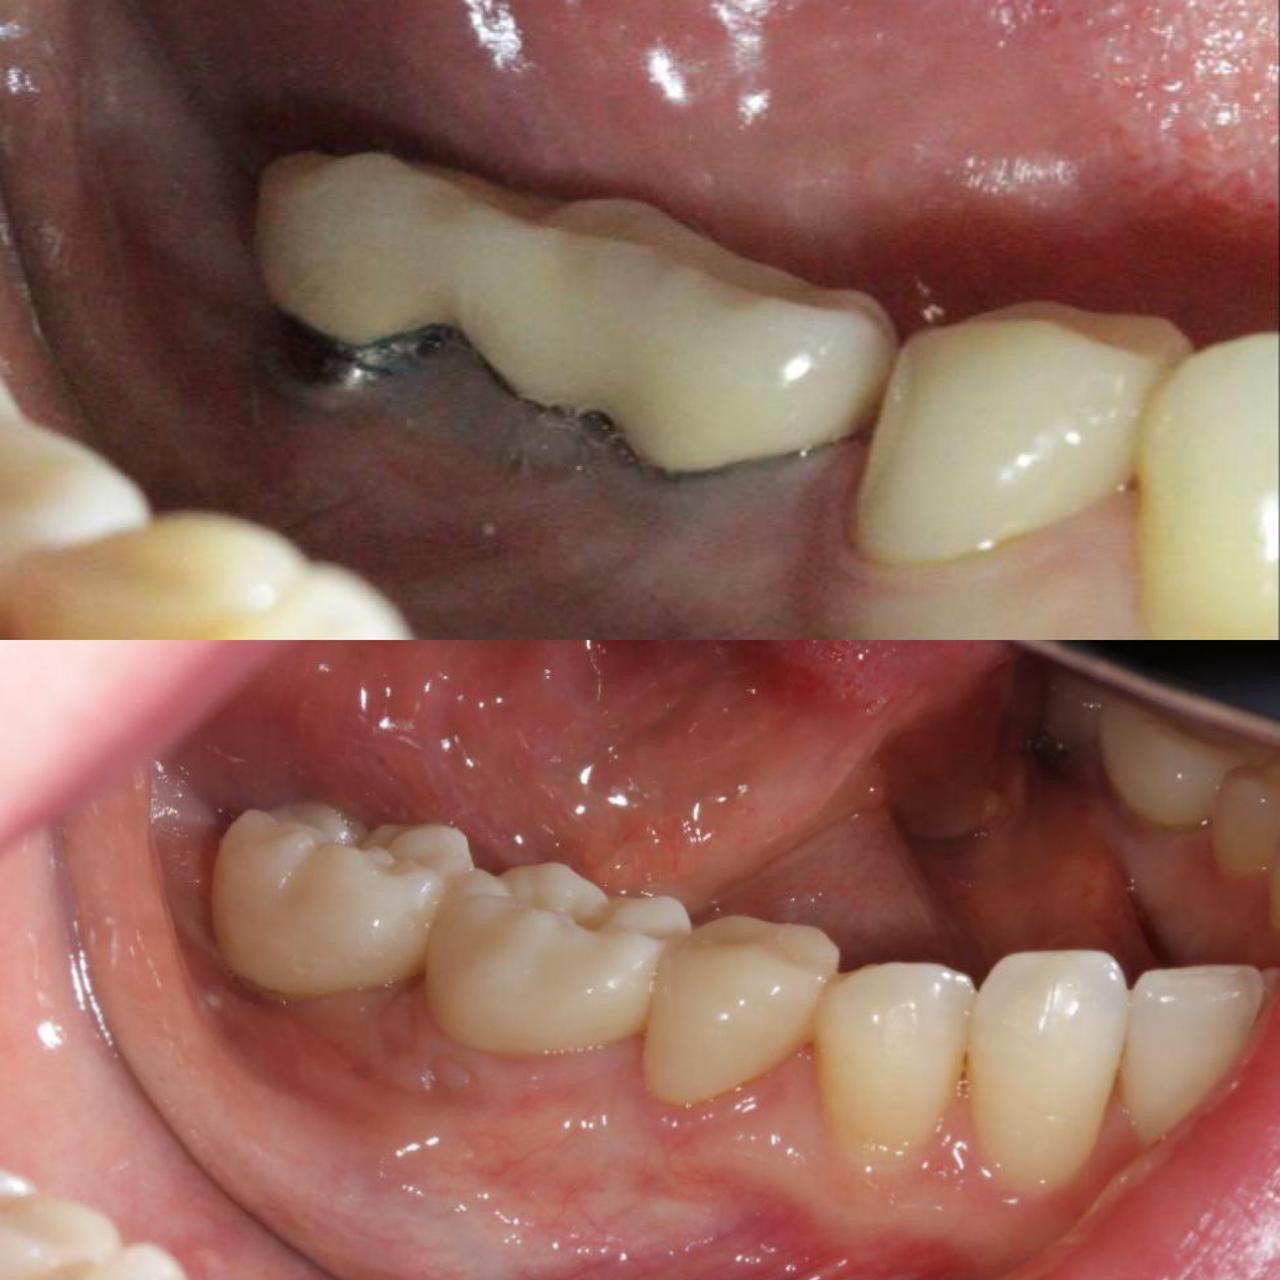

- Восстановление объема мягких тканей перед, во время и после имплантации в зависимости от клинической ситуации с помощью соединительнотканного нёбного трансплантата. Пластика слизистой свободным субэпителиальным лоскутом.

- 2018г.Научно-практический курс "Пластика мягких тканей десны в области имплантанта и естественных зубов под руководством японского профессора Dr. Masana Suzuki

- 2016г.Повышение квалификации. Курс «Мукогингивальная хирургия вокруг зубов»